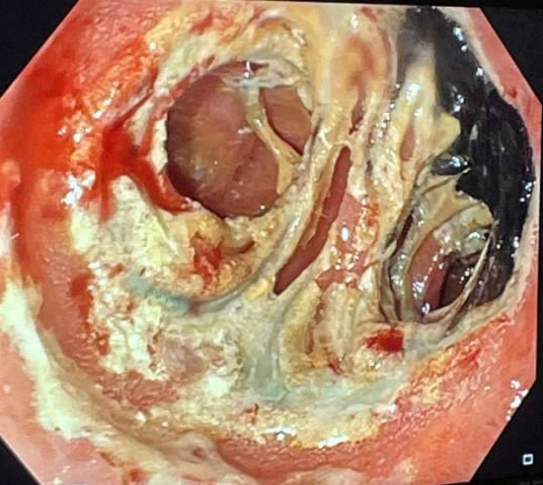

75-year-old man with chronic kidney disease on hemodialysis, atrial fibrillation and history of Roux en-Y gastric bypass was admitted with cholangitis from bile duct stones. His blood culture grew Escherichia coli, klebsiella pneumoniae and Enterococcus faecium. EUS directed trans-gastric ERCP (EDGE) was planned. EGD showed severely inflamed gastric pouch with a large marginal ulcer (Fig A). The patient was too unstable for Lap assisted ERCP. The patient underwent successful single session EDGE with placement of a 20 mm x 10 mm Axios stent (Boston Scientific Corp, Marlborough, Mass, USA) through an area that did not involve the large ulcer (Fig B). Plastic stent was placed initially and two weeks later, the stones were successfully removed using cholangioscope and EHL. Four weeks later EGD showed gastro gastric fistula (Fig C) and LAMS has been spontaneously expelled. The ulcer has completely healed. The fistula was closed after APC ablation by endoscopic suturing (using Apollo Endo stitch) (Fig D). Patient was discharged in stable condition and follow up one month later the patient was doing well.

Figure A, B, C, D